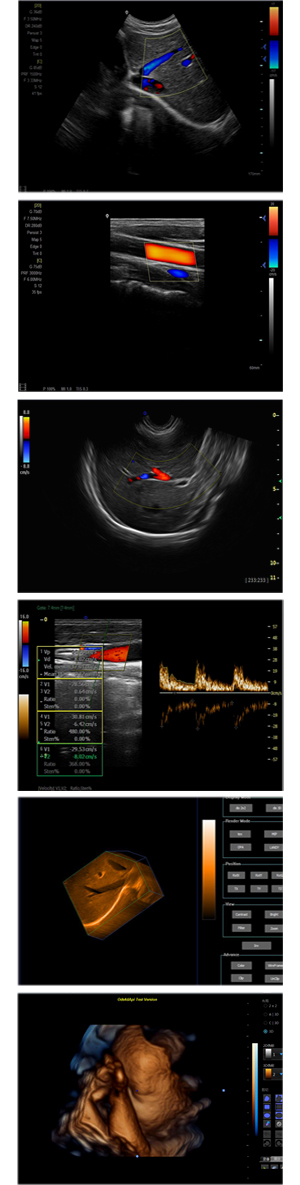

XF-7700型,秉承先鋒彩超技術(shù)之精華,擁有高雅大氣的獨(dú)特外型,為最新一代應(yīng)用型數(shù)字彩色多普勒診斷系統(tǒng),魅力與實(shí)力相融合??蓮V泛適用于腹部、婦產(chǎn)科、心臟、小器官、乳腺、肌骨及外周血管等諸多方面的診查,讓您在臨床超聲診斷應(yīng)用領(lǐng)域得心應(yīng)手,綻放異彩!

突破的成像技術(shù)

● 3D/ 4D成像技術(shù)/選配

● 應(yīng)用于腹部、腎臟、泌尿系統(tǒng)、產(chǎn)科、婦科、盆腔、大動(dòng)脈、肌肉組織、小器官、乳腺、心臟等

● 能量多普勒成像(PDI)

● 彩色血流量圖(CDE)

● 脈沖頻譜多普勒成像(PW)